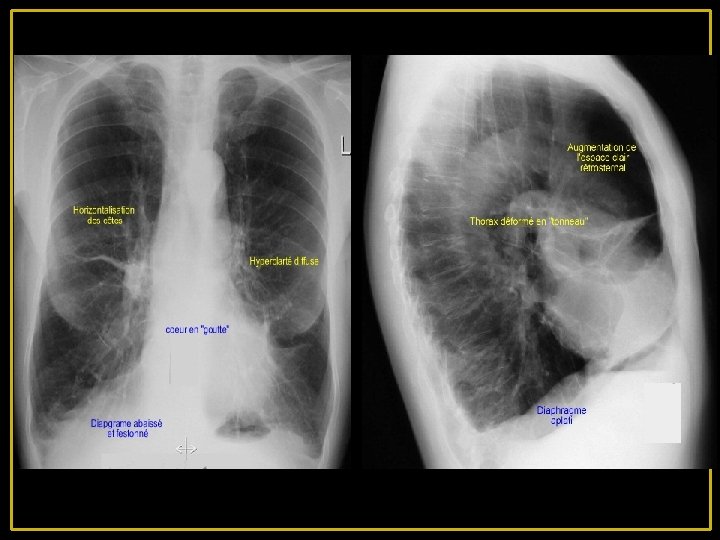

2 - A l'examen physique : A- Inspection: • thorax distendu, en tonneau reste rose : Pink – Puffer • pas d'hippocratisme digital ni de cyanose, B- Percussion: • on note une hypersonarité thoracique C- auscultation: • hypoventilation diffuse • silence auscultatoire aux bases.

4 -Radiologie : - Distension thoracique majeure avec hyper clarté pulmonaire diffuse par raréfaction de la trame vasculaire. - L'existence parfois des bulles d'emphysème siégeant aux lobes inférieurs - Le cœur est petit, allongé, décollé de la coupole dit en « goutte » .